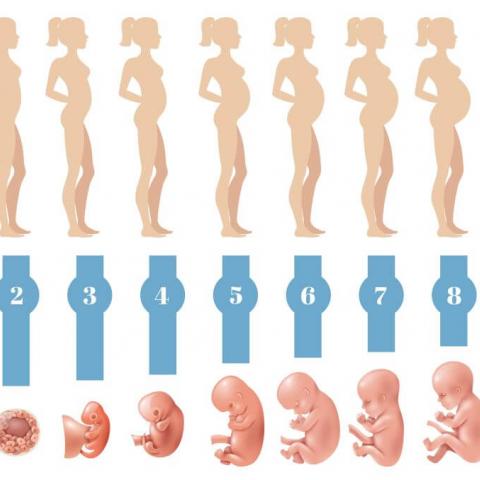

Náplní činnosti porodnického oddělení nemocnice v Kadani je komplexní péče v těhotenství, při porodu a v šestinedělí. Jsou zde léčeny choroby přidružené k těhotenství a choroby komplikující těhotenství porod a šestinedělí. Na porodním sále jsou vedeny porody fyziologické, rizikové (porod koncem pánevním) i komplikované s možností operačního ukončení. Na oddělení je zaveden kompletní systém péče o novorozence "rooming-in", tj. maminka má dítě stále u sebe s výjimkou případů, kdy se o ně nemůže starat (stav po císařském řezu, nutnost intenzivní péče o nedonošené děti apod.).